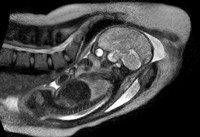

Gimdymas vyko sklandžiai ir gydytojai galėjo stebėti pirmųjų gimimo pakopų trimatį vaizdą. Anksčiau panašiais skeneriais ir zondais tokio detalumo pasiekti nebuvo įmanoma arba dėl techninių apribojimų, arba dėl pernelyg didelio motinai ir kūdikiui keliamo pavojaus. Specialistų komandoje dalyvavęs gydytojas Christianas Bambergas vėliau teigė, jog įrašytuose vaizduose galima stebėti vaisiaus judesius gimdymo kanale, kaip juda jo kaulai ir kaip gimimo metu keičiasi jo galvos forma. Visa ši informacija gali padėti paaiškinti gimdymo eigos sutrikimus, dėl kurių neišvengiamai tenka atlikti Cezario pjūvį (JAV tokiu būdu baigiasi apie 30 procentų visų gimdymų).